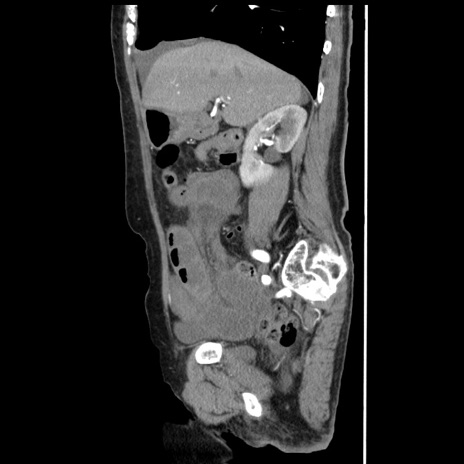

横断像

【症例】80歳代女性

【主訴】腹痛

【現病歴】8時間前から腹痛あり来院。

【既往歴】糖尿病、脂質異常症、子宮体癌にて子宮全摘術

【身体所見】意識清明・会話良好だが腹痛で苦悶様、全腹部にわたって反跳痛と圧痛あり

【データ】WBC 13600、CRP 0.14、LDH 224、CK 90